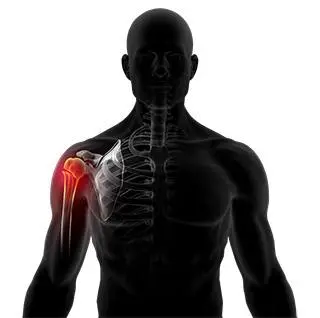

Shoulder Fracture

Shoulder Fracture Care